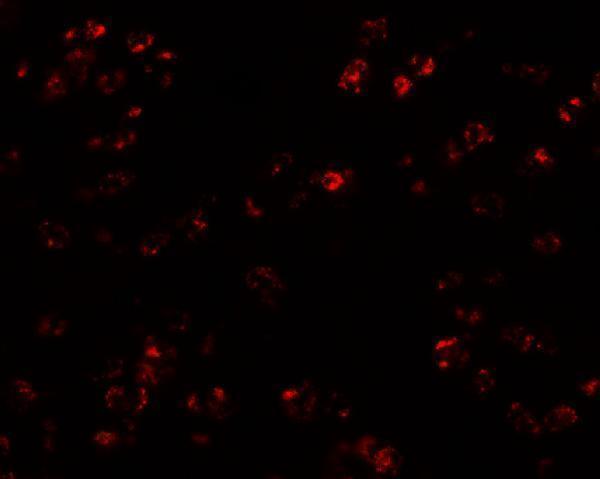

Facts about C-C motif chemokine 17.

Binds to CCR4. .